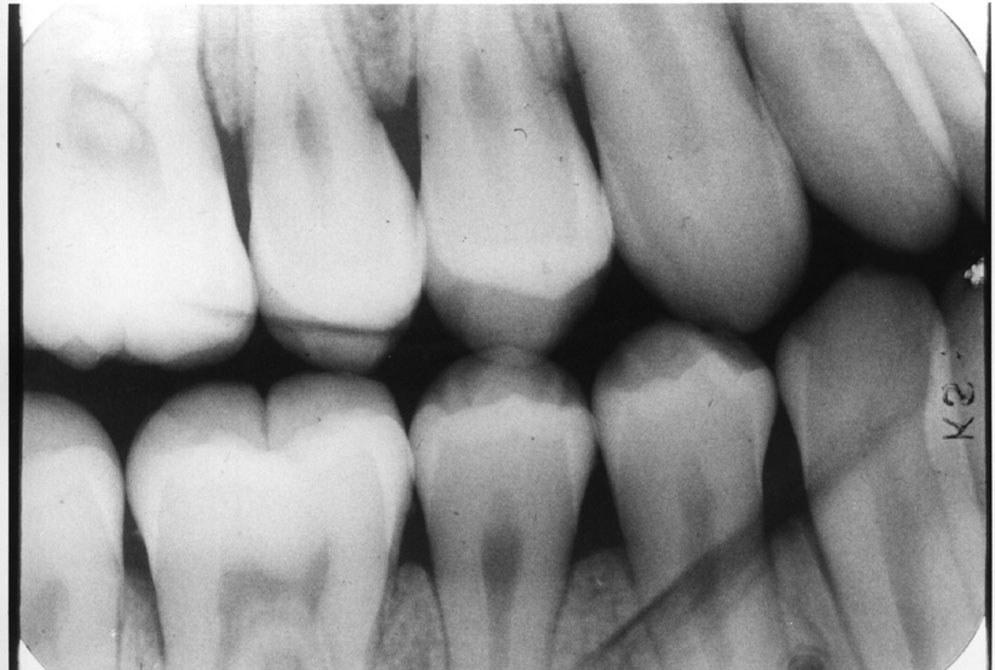

Figure 5. Example showing distance between cusps.

Figure 5

Foreshortening

Description: Foreshortening occurs when the central ray from the tubehead is too high, making the vertical beam angulation too steep. The image appears shortened particularly at the portions of the teeth that were closest to the beam (Figure 4).

Differential Diagnosis: Visible shortening of the teeth, with somewhat wider appearance of objects closest to the x-ray head. The incisal or cuspal edge may be partially missing. The posterior teeth may show a greater distance between the buccal and lingual cusps (Figure 5).

Consequences: The image may still be acceptable, despite the error. If the foreshortening interferes with the film’s diagnostic quality, a retake is necessary.

Remedy: The operator should review technical procedures regarding vertical angulation in relation to Paralleling technique or Bisect-the-Angle technique and repeat the film. The operator should decrease the vertical angulation in order to correct foreshortening of an image.